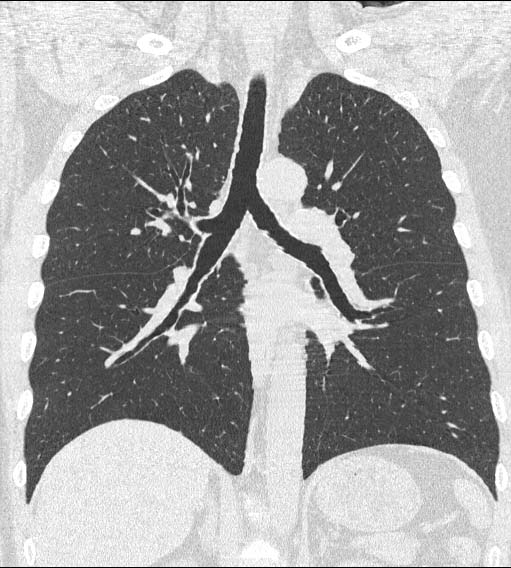

Advanced Aquilion Prototype (8-row)

Clinical example #2

Normal Chest

0.5mmx8, pitch 10,